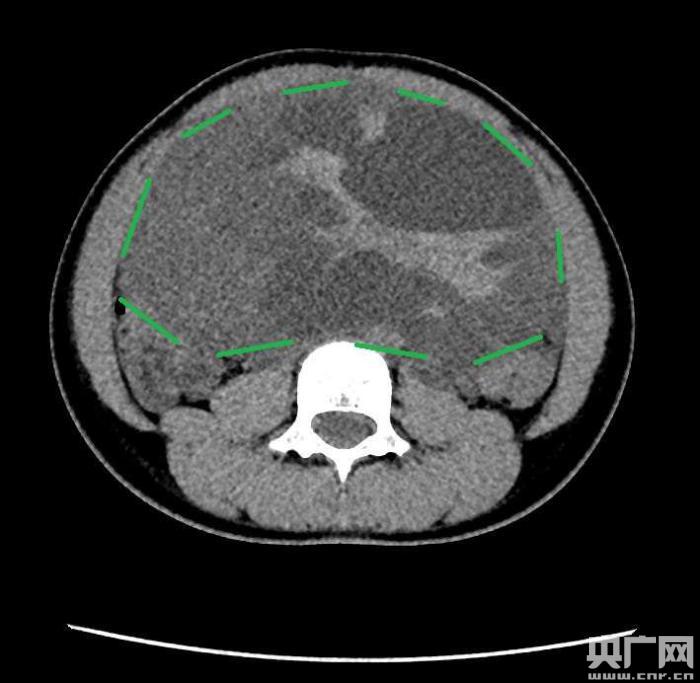

入院后,普外一科肖東主任向家長(zhǎng)詢問(wèn)了病史,仔細(xì)進(jìn)行了體格檢查,并完善腹部CT。CT結(jié)果提示,孩子的大部分腹腔、盆腔被一個(gè)巨大的腫瘤占據(jù),腸道、血管和腎盂都受到了不同程度的壓迫。從CT上看,腫瘤很可能起源于左側(cè)的卵巢。

手術(shù)中發(fā)現(xiàn),小琪腹中的腫瘤體積巨大,大小約為25×20×15厘米,表面光滑,來(lái)源于左側(cè)卵巢。醫(yī)生們首先將其與周圍的組織小心剝離,然后將這個(gè)占據(jù)孩子腹腔、盆腔大部分的巨大包塊完整切除,切除腫瘤后還重建了左側(cè)卵巢。剖開(kāi)瘤體,發(fā)現(xiàn)瘤體為囊性及實(shí)性混合組成,瘤體內(nèi)部充盈著粘液狀的液體,重量達(dá)到了3000克。術(shù)后小琪病情穩(wěn)定,測(cè)量腹圍從術(shù)前的72厘米減小到了62厘米。